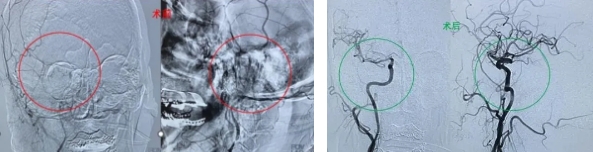

【病例2】为84岁的退休老人陈某,于7月31日突发言语障碍、左侧肢体活动受限及意识模糊,持续半小时后被家人紧急送入第十师北屯市总医院急诊科。医院迅速激活脑卒中救治绿色通道,援疆专家张士存副主任与受援科室神经医学科(卒中中心)负责人顾晓泓第一时间开展救治,立即展开全面检查与评估,确诊为急性脑梗死,病因疑为急性大血管闭塞。经家属同意,决定实施“溶栓+取栓”联合治疗方案,首先给予阿替普酶静脉溶栓,DNT时间仅29分钟,遗憾的是,患者症状未见改善。随后,紧急安排脑血管造影术,明确诊断为右侧颈内动脉闭塞伴串联病变,病情复杂,治疗难度与风险均极高,对技术与材料要求严苛。考虑到转至乌鲁木齐、石河子等地医院抢救会错过最佳时间,家属最终决定继续在医院接受治疗。医院随即为患者实施全身麻醉下的“动脉溶栓+球囊扩张血管成形术+机械取栓(抽吸)”综合手术,术中巧用“冠状动脉介入球襄导管”进行血管成形术和机械取栓(抽吸),手术过程顺利,成功再通右侧颈内动脉前循环系统,恢复大脑正常血流,并为患者节省数万元。术后,患者被转入重症医学科进行综合治疗,并于术后首日恢复意识,偏瘫侧肢体肌力显著提升,从0级恢复至III+级,四肢能按指令活动。目前,患者恢复状况良好,拟转至普通病房接受进一步的康复治疗。(来源:新疆建设兵团第十师北屯市总医院 责编:宣传科 吕唱 一审:于海明 二审:高秀文 三审:刘波 )